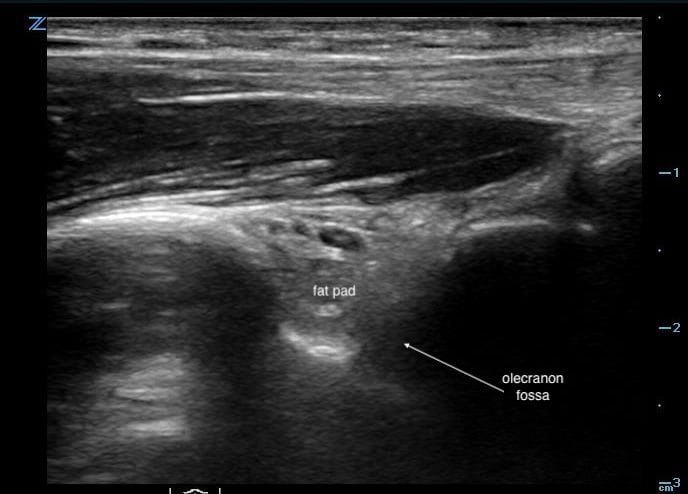

- Alternatively, the elbow may be viewed posteriorly, with the patient’s elbow held in 90-degree flexion and the transducer placed in the transverse orientation. (Fig. 12)

- Figure 12. Transducer placement for posterior elbow joint arthrocentesis

- Posterior fat pad is seen within the “valley” of the olecranon fossa. (Fig. 13)

- Figure 13. Ultrasound image demonstrating normal posterior fat pad

- Hypo/anechoic effusion will displace the fat pad “upwards” out of the fossa, giving impression of an “overflowing cup” sign. (Video 5)

- Video 5. Ultrasound demonstrating displacement of posterior fat pad by effusion